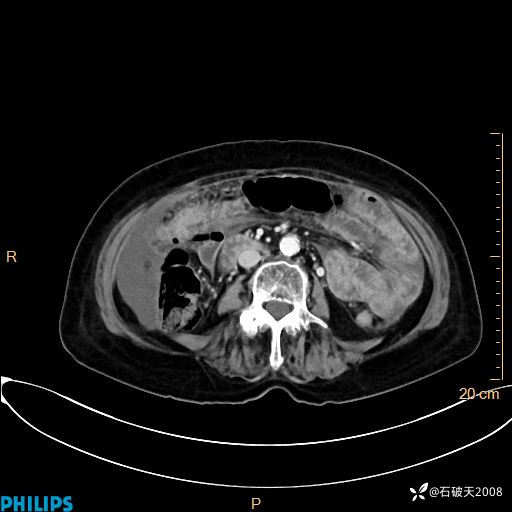

动脉期